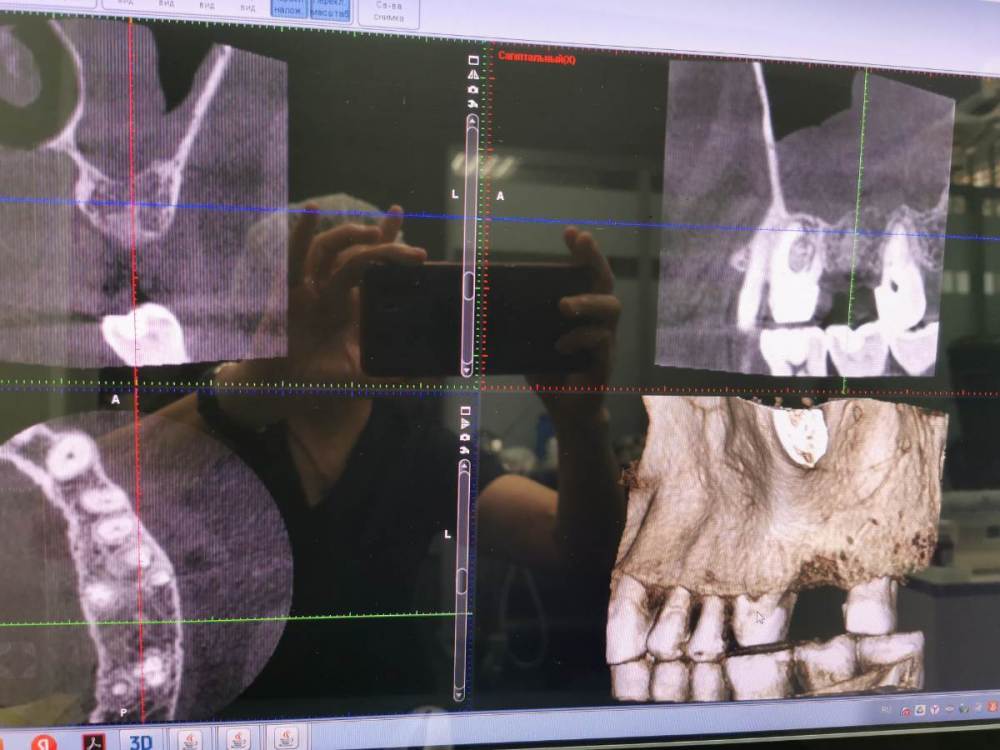

Женька Опубликовано 23 апреля, 2023 Поделиться Опубликовано 23 апреля, 2023 Коллеги, здравствуйте. Вопрос собственно в названии темы. около 4 месяцев назад я удалял зуб. Удаление атравматичное, распилил, аккуратно расклинил. В лунку губку только укладывал, обычный коллаген (Стимул-Осс), швы.Заживление без особенностей. срез "до" Ссылка на комментарий

kramer Опубликовано 23 апреля, 2023 Поделиться Опубликовано 23 апреля, 2023 TL + синус-лифт 2 Ссылка на комментарий

Женька Опубликовано 25 апреля, 2023 Автор Поделиться Опубликовано 25 апреля, 2023 @TIGER я понимаю, что выгляжу нелепо, но при таком сильном воспалении я не уложил бы ничего... да и пациентка пытается всячески выползти финансово. Поэтому посчитал варианты с сеткой и без. Кстати первичная адентия 2.5. В сторонней клинике сказали, что только 2 имплантата ставить и никак иначе. Я конечно цифровоск не делал, но ка по мне либо 2 премоляра зайдут, либо крупный моляр, либо средний моляр и куцый премоляр. И всё это я бы делал на одном имплантате, что думаете коллеги?@kramer @TIGER Ссылка на комментарий

TIGER Опубликовано 25 апреля, 2023 Поделиться Опубликовано 25 апреля, 2023 @Женька про нелепо перегнул?я не вижу там сильного воспаления,поэтому провёл бы через аллографт&ptfe ,через 2-3 мес закрытый синус;)максимум .По поводу кол-ва имплантов,тут конечно постановка в проге нужна.если речь об одном импланте,то это TL широкая платформа.по поводу того,что пациентка пытается "выползти финасово" в итоге будет виноват доктор…поэтому нет бюджета,когда будет заходите ,обсудим)не надо закладывать себе проблему на будущее Ссылка на комментарий

DoctorT Опубликовано 26 апреля, 2023 Поделиться Опубликовано 26 апреля, 2023 16 часов назад, Женька сказал: @TIGER я понимаю, что выгляжу нелепо, но при таком сильном воспалении я не уложил бы ничего... да и пациентка пытается всячески выползти финансово. Поэтому посчитал варианты с сеткой и без. Кстати первичная адентия 2.5. В сторонней клинике сказали, что только 2 имплантата ставить и никак иначе. Я конечно цифровоск не делал, но ка по мне либо 2 премоляра зайдут, либо крупный моляр, либо средний моляр и куцый премоляр. И всё это я бы делал на одном имплантате, что думаете коллеги?@kramer @TIGER А вот цифровоск я бы сделал до всех манипуляций, мы же иплантанты ставим не ради имплантантов, а ради зубов. Один широкий моляр не катит, два премоляра либо ортодонтия. Ссылка на комментарий